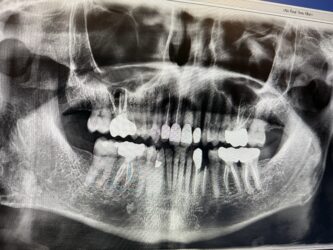

Looking for some feedback and advices. #21 was extracted and placed immidate 4.1×12. I know I needed to go 2-3 mm beyond the apex, however, I didn’t have the correct length. The final torque was about 20 NCM. Bone graft was added and collagen plug and sutured with chromic gut. Please evaluate the radiographs and advise. When should I schedule for follow up?

Everything looks fairly solid on the xray to me. I would follow up 4 weeks post op and see how things are progressing.